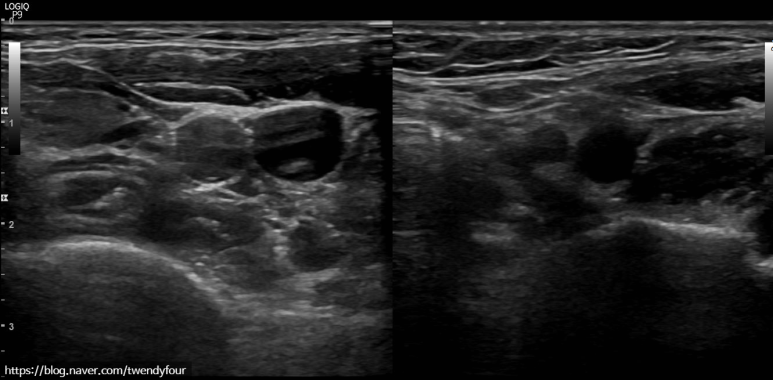

경동맥은 내경동맥(ICA;머리로의 혈관), 외경동맥(ECA;얼굴로의 혈관)으로 나뉘는 분지부가 다른 부분보다 굵어지므로 반드시 혈관벽 상태를 측정합니다.

45세 남성, 경동맥 혈관 벽이 60% 좁아져 있다.

만약 혈관 벽이 두꺼워지고 혈관 벽이 좁아졌다면 얼마나 두꺼워졌는지 퍼센트로 경동맥 협착증을 확인합니다.정밀경동맥 초음파 검사는 경동맥 혈관 벽이 50% 이상 두꺼워진 분에게 더 깊이 들어갑니다.

경동맥 중의 내경동맥, 머리에 혈관의 정밀 경동맥 초음파 검사 사진입니다.

반대편 왼쪽도 경동맥 검사가 똑같이 들어갑니다.

혈관 벽이 두꺼워졌는지 측정합니다.